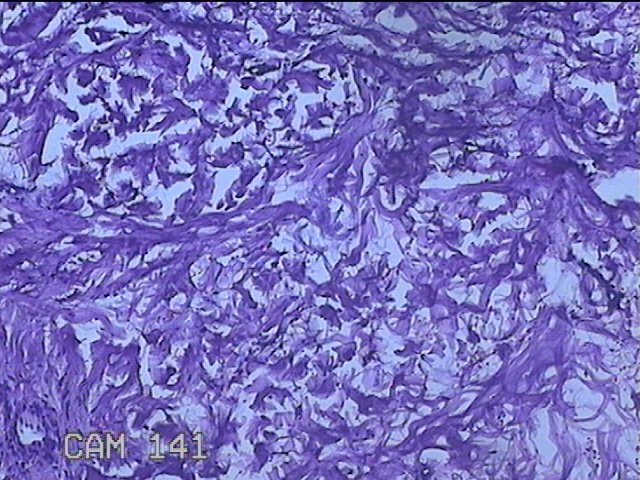

左侧臀部结节

性别

男

年龄

40岁

临床诊断

皮下结节

一般病史

发现左侧臀部结节1年余。

标本名称

大体所见

灰白粉红色组织1.3x0.8x0.3cm一块,表面带梭形皮肤1.3x0.8cm,皮下见结节1.3x1x0.7cm一个,切开结节呈实性,切面灰白粉红色,质软。

图4